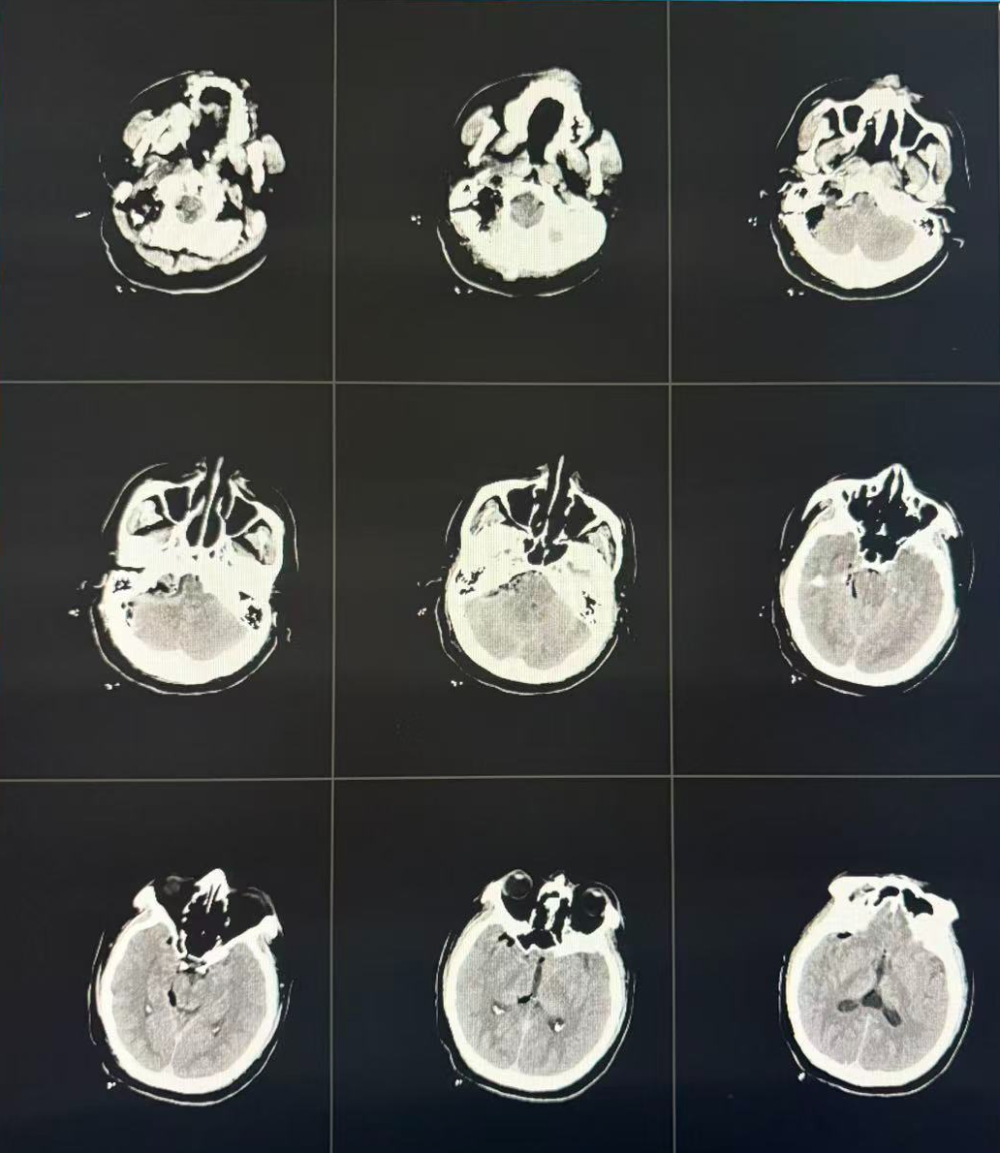

术后CT检查

考虑到肿瘤位置深在、累及桥小脑角及颈静脉孔区,且毗邻脑干及重要神经血管,手术难度与风险极高。为最大程度保障患者安全并保护神经功能,纪文军团队联合麻醉手术科等多学科展开术前讨论,最终制定个体化方案:借助神经电生理监测技术,通过耳后隐蔽弧形切口,采用“远外侧入路”这一精准路径实施肿瘤切除。经过充分术前准备,在纪文军主任医师领衔下,杜彦挺主任医师、张伟副主任医师及黄子钊主治医师团队默契配合,在麻醉手术科全程护航下,历时3小时成功完整切除肿瘤。

术后病理结果显示为神经鞘瘤。经过两周精心治疗与护理,患者生命体征平稳,面瘫、声嘶、饮水呛咳等问题均得到显著改善,并康复出院。此次手术的成功,充分展现了交大一附院榆林医院在复杂颅底肿瘤诊疗领域的技术突破,为陕甘宁蒙晋交界区群众提供了更优质的医疗保障。